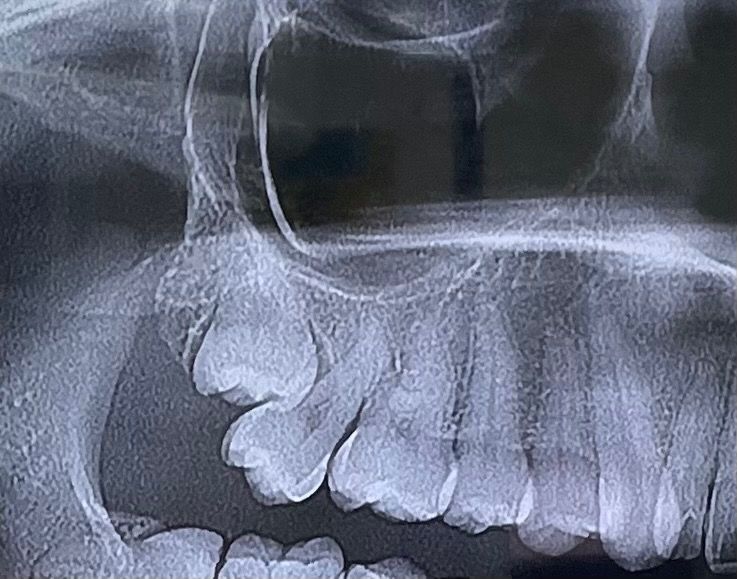

치과에서 사랑니가 안좋게 나서 사랑니 앞 어금니가 안좋아질수 있다고 발치 추천하셨어요. 그래서 유명한 사랑니 발치 전문 치과에 갔는데 사랑니 뽑다가 어금니 같이 뽑히거나, 사랑니만 뽑히더라도 어금니가 많이 흔들려서 밥먹다가 빠질수도 있다네요.

그리고 다른 사랑니발치 전문 치과에 문의해보니 발치가 가능하다던데, 발치하는게 좋을까요? 저는 어금니 임플란트 안하고 오래오래 쓰고싶어서 고민입니다!

사진상에 보이는 사랑니는 매복되어 잇어서 특별한 이유가 없다면 발치를 하지 않으셔도 될것같습니다.

사진으로 봤을 때는 사랑니가 맹출되지 않은 것으로 보입니다. 사랑니가 매복되어 있고 다른 문제를 발생시키지 않는다면 발치하지 않아도 됩니다.

발치를 하지 않으면 앞 어금니에 안 좋은 영향(충치유발, 치근흡수)도 있을 수 있지만 반면 뺄때도 앞 어금니에 영향을 줄 수도 있습니다 각도상 어쩔 수가 없네요

일단 매복된 오른쪽 윗쪽 사랑니 발치하는 것이 좋습니다. 그냥두면 점점 더 바로앞 어금니가 상하게 됩니다. 이런 경우 대개의 경우 바로앞 어금니 살릴 수 있습니다.